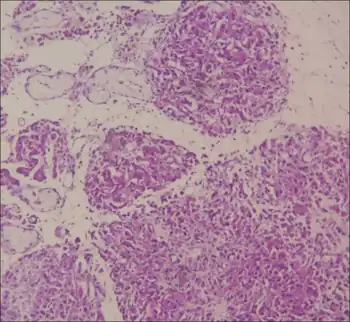

Under the microscope, some samples taken for biopsies displayed results where testicular tissue was at a stage of immaturity, and showed dysplasia.[9]

PMDS patients have a possibility of infertility in the future if not promptly operated on. When the affected males are adults, those who are not aware of the condition may find the presence of blood in their semen (hematospermia).[17] The Müllerian structures and cryptorchidism can also develop into cancer if ignored, or if there are pieces of Müllerian structures left from past surgery.[17] If PMDS is found during adulthood, or if Müllerian structures had to be left behind due to risks in surgery, biopsies of the remaining Müllerian structures can be performed. Upon pathohistological observation, the endometrial tissues appear atrophied, and the fallopian tubes have begun to congest showing signs of fibrosis.[17]